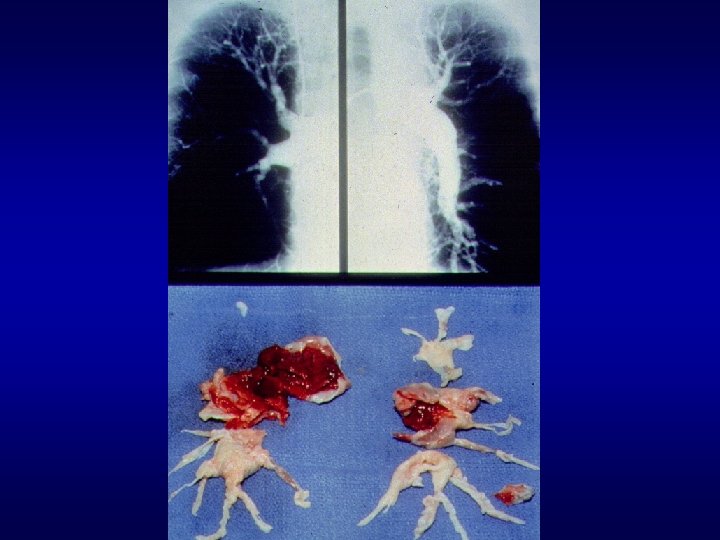

Lung with PE